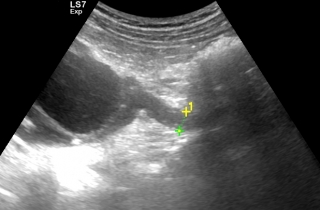

Kamica nerkowa

Kamica to jedno z częstszych schorzeń układu moczowego. Kamień, który wydostanie się z nerki i utknie w moczowodzie blokuje odpływ moczu powodując tzw. wodonercze oraz kolkę nerkową. W #KlinikaBulwarDedala leczymy kolki nerkowe.